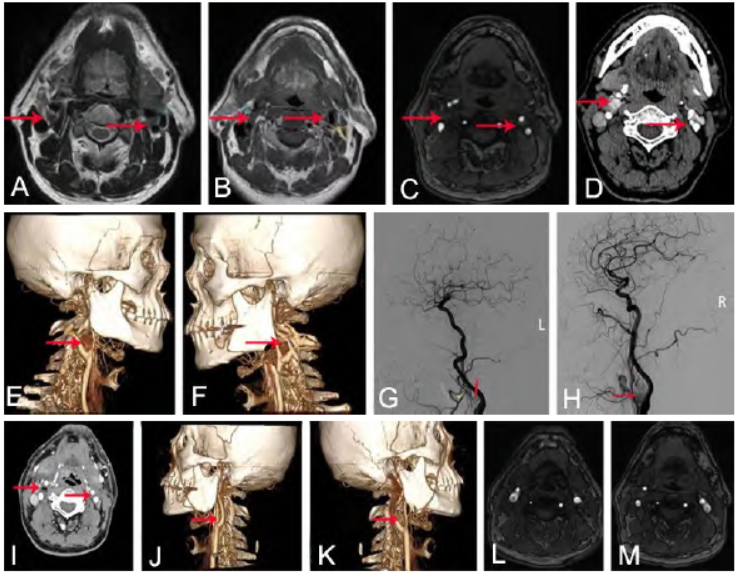

图1 双侧颈动脉体瘤手术前后影像。A. 术前MRI T2像显示双侧颈总动脉分叉处团块状高信号(红色↑示);B. 术前MRI T1像显示双侧颈总动脉分叉处团块状等信号(红色↑示);C. 术前MRA显示双侧颈内动脉向后外侧移位,双侧颈外动脉向前内侧移位(红色↑示);D~F. 术前CTA显示双侧颈外动脉与颈内动脉间隙内可见一类圆形结节影,增强后呈不均匀强化,与右侧颈内、外动脉分界较清(红色↑示);G、H. 术前DSA显示双侧颈内动脉和颈外动脉间类圆形肿物(红色↑示),血供丰富;I~K. 术后1周复查CTA显示双侧颈部脂肪间隙多发类圆形气体影,肿瘤切除干净;L、M. 术后6个月复查头颅MRA未见肿瘤复发

颈部CTA示双侧颈外动脉与颈内动脉间隙内可见一类圆形结节影,大小分别为1.2 cm×1.3 cm×4.7 cm(右)、0.8 cm×0.8 cm×1.3 cm(左),增强后呈不均匀强化,与右侧颈内、外动脉分界较清。

右侧颈总动脉造影可见颈动脉分叉处CBT形成,并有右侧颈外动脉血供形成;左侧颈总动脉造影可见颈动脉分叉处颈动脉体瘤(carotid body tumor,CBT)形成,并有左侧颈外动脉血供形成。

2周后行右侧肿瘤切除术(Shamblin分型Ⅱ型;PUMCH分型Ⅲ型),予以锐性分离肿物,术后病理诊断CBT。术后3 d头晕及视物模糊明显改善,术后3个月症状完全消失。术后1周复查颈部CTA见双侧颈部脂肪间隙多发类圆形气体影,肿瘤切除干净,呈术后改变。术后6个月复查头颅MRA未见肿瘤复发。